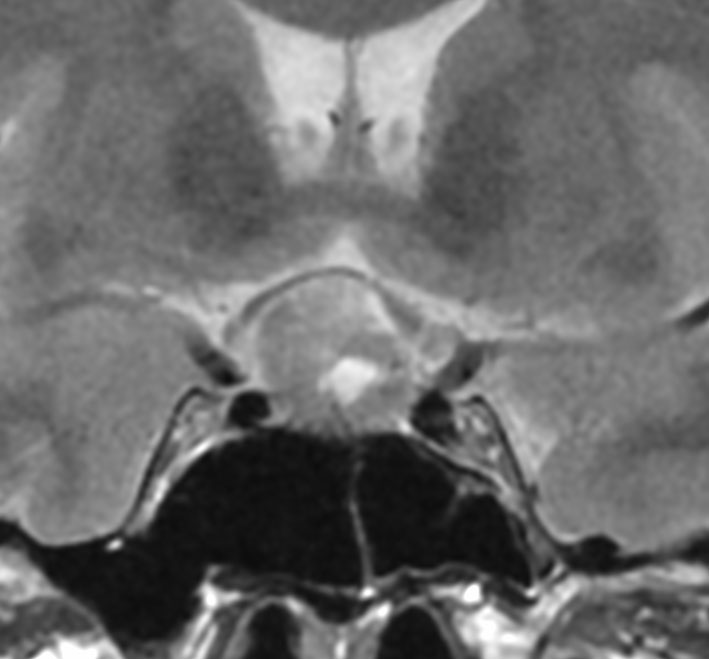

下垂体後葉腫瘍の典型的な画像です。下垂体柄(黄色の矢印)が伸びて前方へ偏移しています。またその直下に下垂体前葉(強い白の部分)がみえます。

ジャーミノーマでは下垂体柄も同時に太くなるのでジャーミノーマは否定的な所見です。

MRIとCTでは後床突起の上に乗っているように見え,後床突起髄膜腫とも紛らわしいです

この例は下垂体柄が認識できて,灰白隆起から発生したとしか思えませんでした

40代の女性に,軽度の両耳側半盲で発生したものです。視交叉と視床下部の下面に腫瘍があり,下垂体柄の位置が全くわからず,下垂体の前葉と後葉は侵されていません。ですから,下垂体柄から発生した腫瘍であり,pituicytomaが強く疑われます。T2ではほぼ等信号,小さなのう胞があり,ガドリニウムで強く増強されます。手術では正常下垂体柄の一部が右側にうすく残っており,幸運にも亜全摘出できて下垂体機能は温存できました。残存腫瘍は増大傾向を示していません。でも,このようなタイプを積極的に摘出すると,汎下垂体機能低下症を招くことが多いので,手術するかどうかの判断はとても難しいです。